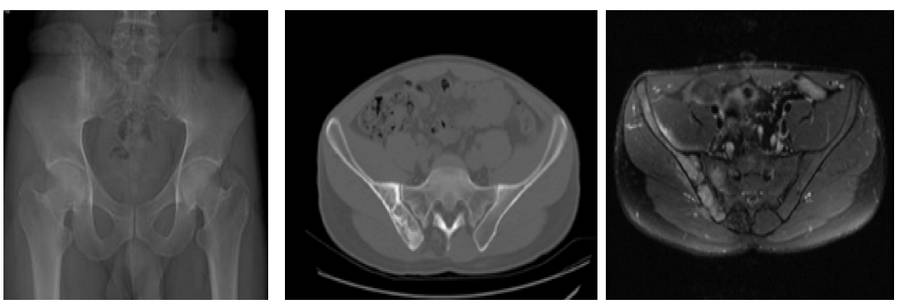

Ameliyat Öncesi: Röntgen, tomografi ve MR’da sağ sakroiliak bölgede düzensizlik ve harabiyet görülmekte